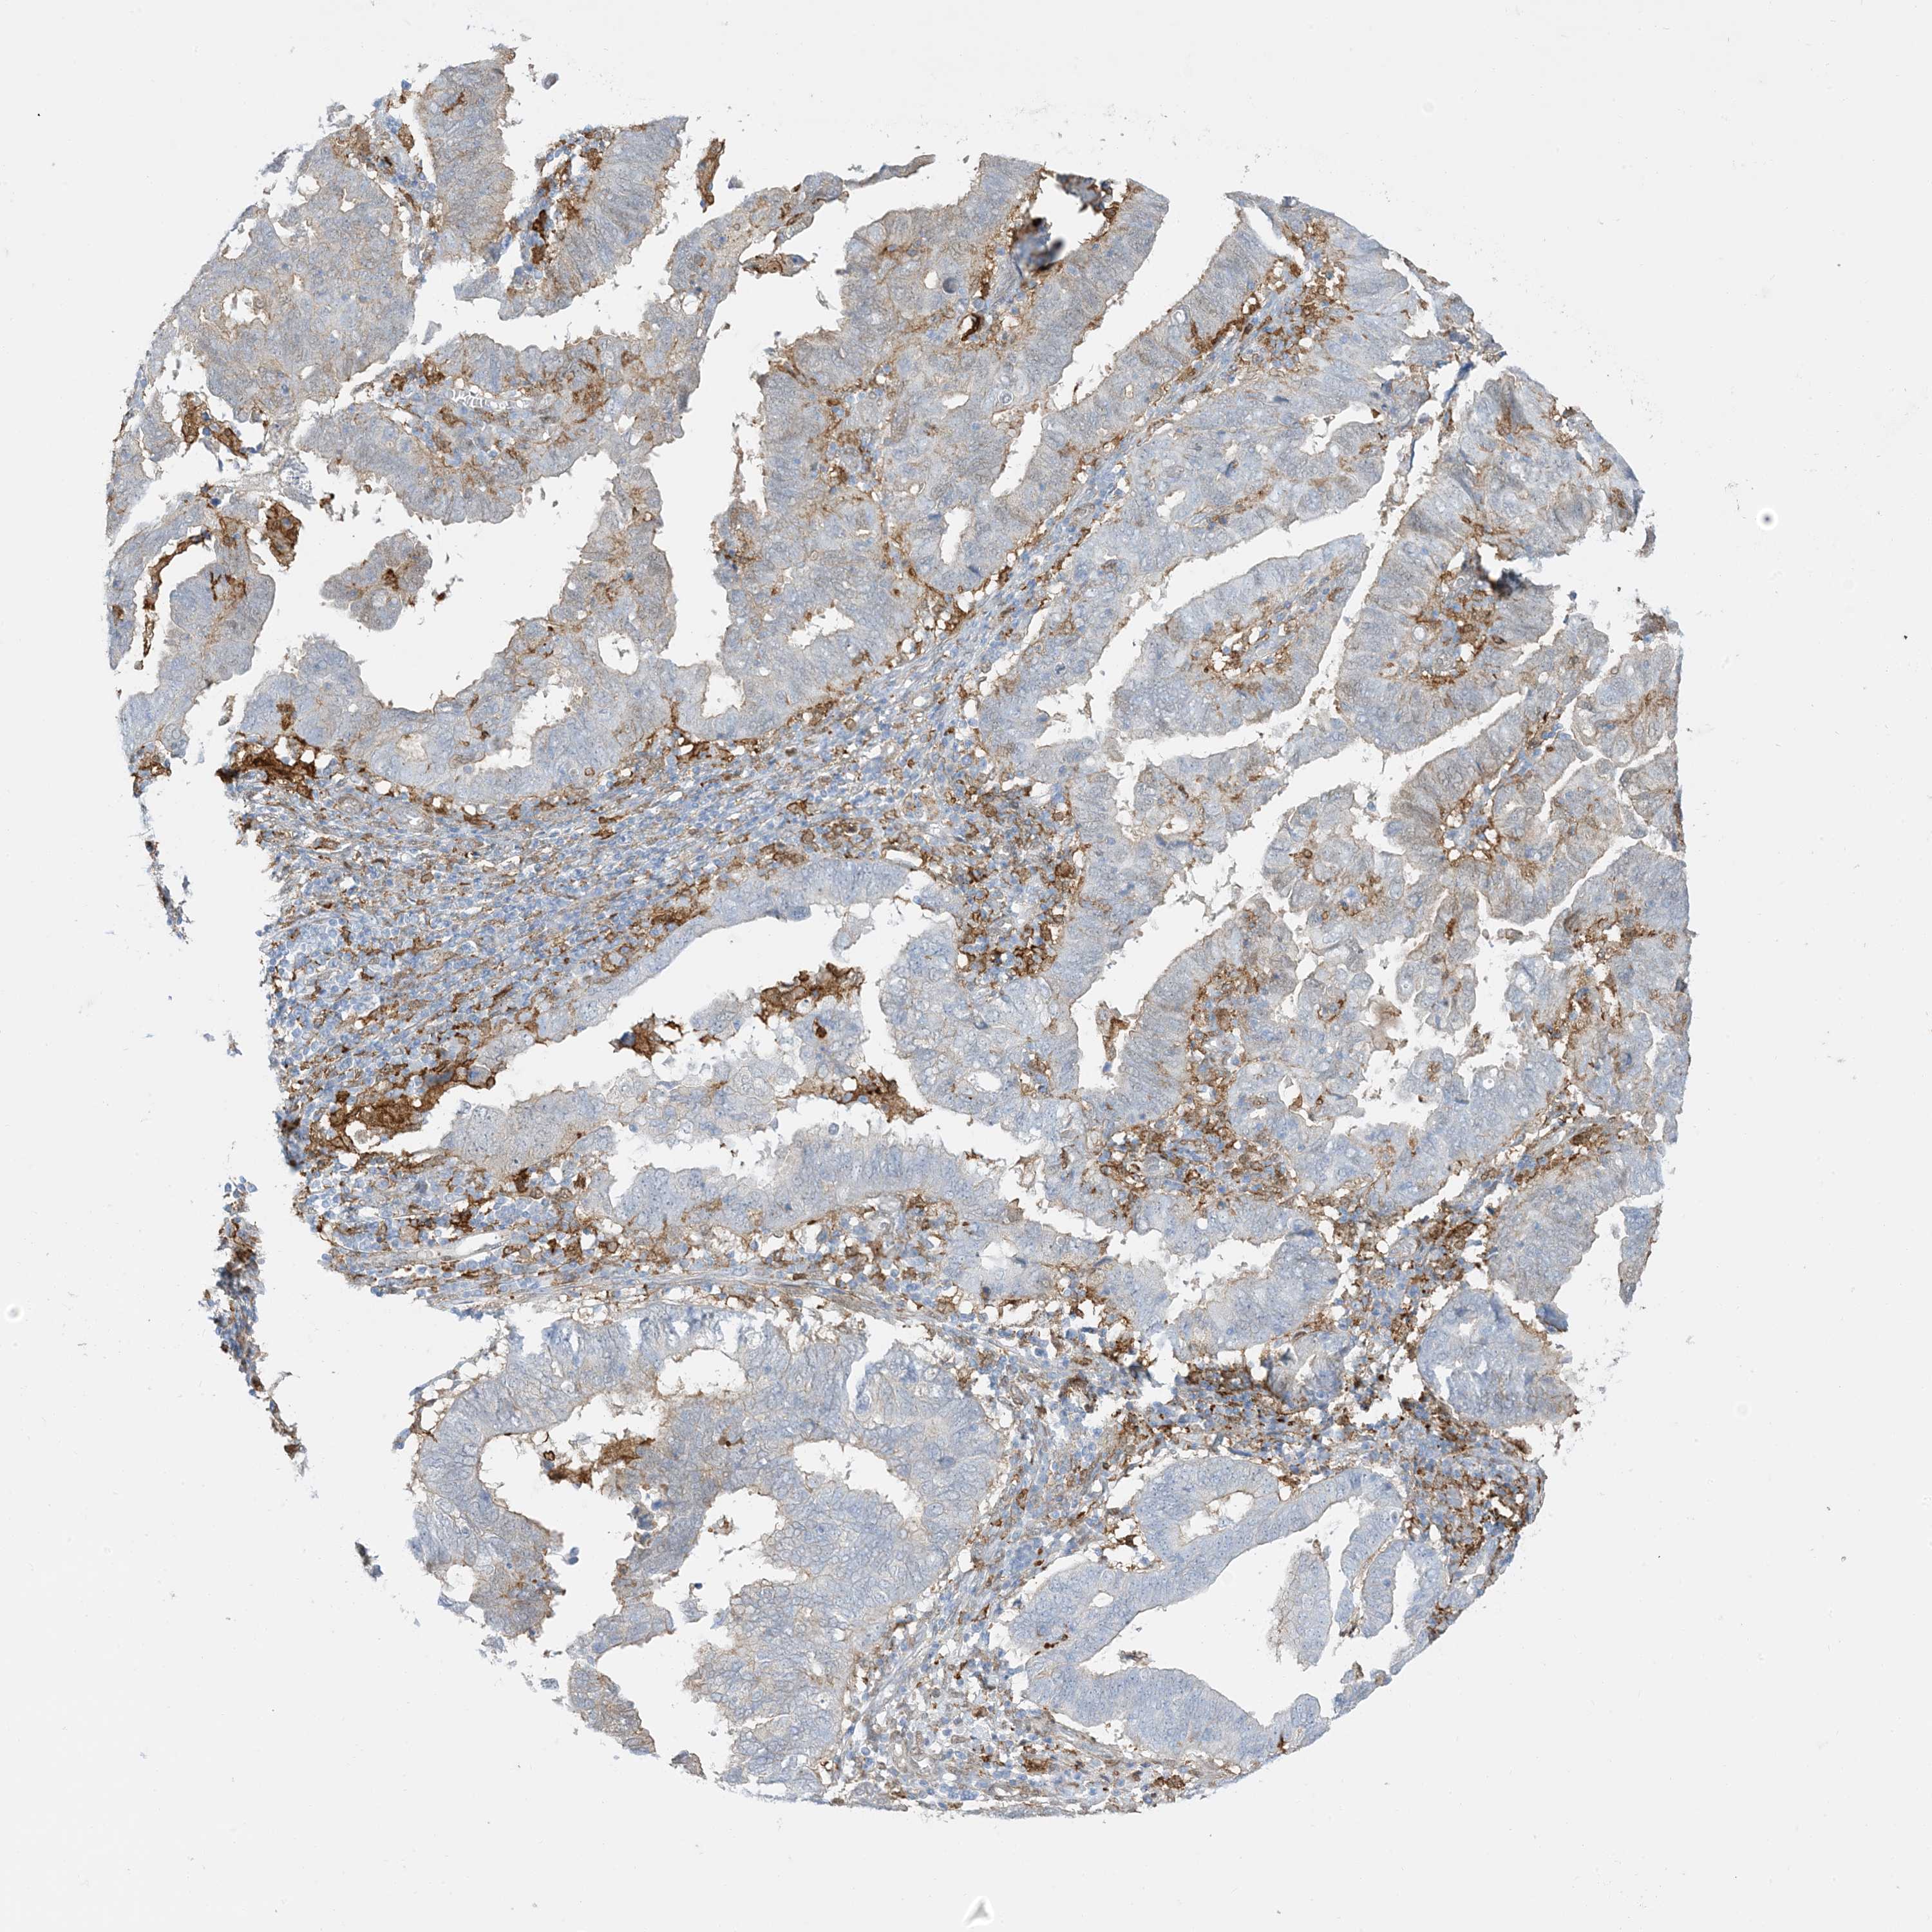

ENDOMETRIAL CANCER - Protein expressioni

A mouse-over function shows sample information and annotation data. Click on an image to view it in a full screen mode. Samples can be filtered based on level of antibody staining by selecting one or several of the following categories: high, medium, low and not detected. The assay and annotation is described here.

Note that samples used for immunohistochemistry by the Human Protein Atlas do not correspond to samples in the TCGA dataset.

Antibody stainingi

Antibody staining in the annotated cell types in the current human tissue is reported as not detected, low, medium, or high, based on conventional immunohistochemistry profiling in selected tissues. This score is based on the combination of the staining intensity and fraction of stained cells.

Each image is clickable and will lead to virtual microscopy that enables deeper exploration of all samples and also displays staining intensity scores, fraction scores and subcellular localization as well as patient and tissue information for each sample.

Antibody HPA054026

Antibody CAB010823

Antibody CAB016728

Antibody CAB036009

Staining

High

Medium

Low

Not detected

Intensity

Strong

Moderate

Weak

Negative

Quantity

>75%

75%-25%

<25%

None

Location

Nuclear

Cytoplasmic/membranous

Cytoplasmic/membranous,nuclear

Adenocarcinoma, NOS

Adenocarcinoma, metastatic, NOS